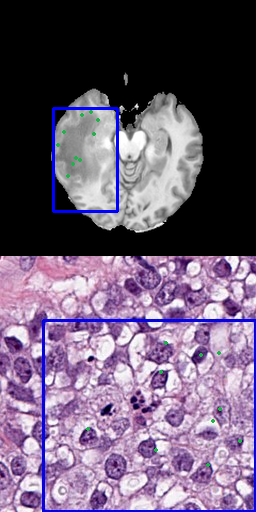

4.4.3 Bounding Box and Points

As using only a bounding box is imprecise but requires low effort for large areas and points are more precisely but tedious to set manually, we also tested the combination of both to compensate for their individual disadvantages: We use 3, 10, 50 and 100 positive input points and combine it with a bounding box that covers a larger area around all of them. Figure 5 shows, samples of these for pathology and radiology.

Refer to caption

(a) 3 points with bounding box

(b) 10 points with bounding box

(c) 50 points with bounding box

(d) 100 points with bounding box

Figure 5: Results for different number of positive points combined with bounding box